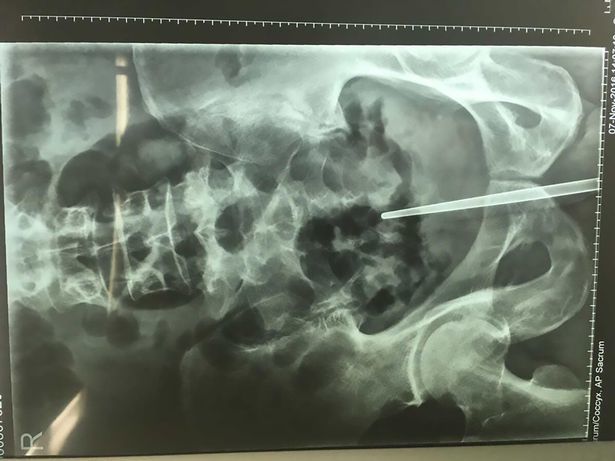

Ông Trần cho hay, ông ta đưa chiếc đũa vào niệu đạo nhưng nó bị kẹt lại và không thể lấy ra nổi, sau đó ông bị đi tiểu ra máu.

Các bác sĩ đã phẫu thuật để lấy chiếc đũa bằng kim loại ra.

Bác sĩ ở bệnh viện TP Hàng Châu cho biết, ông Trần có thể tử vong nếu chiếc đũa bị đẩy vào sâu hơn.